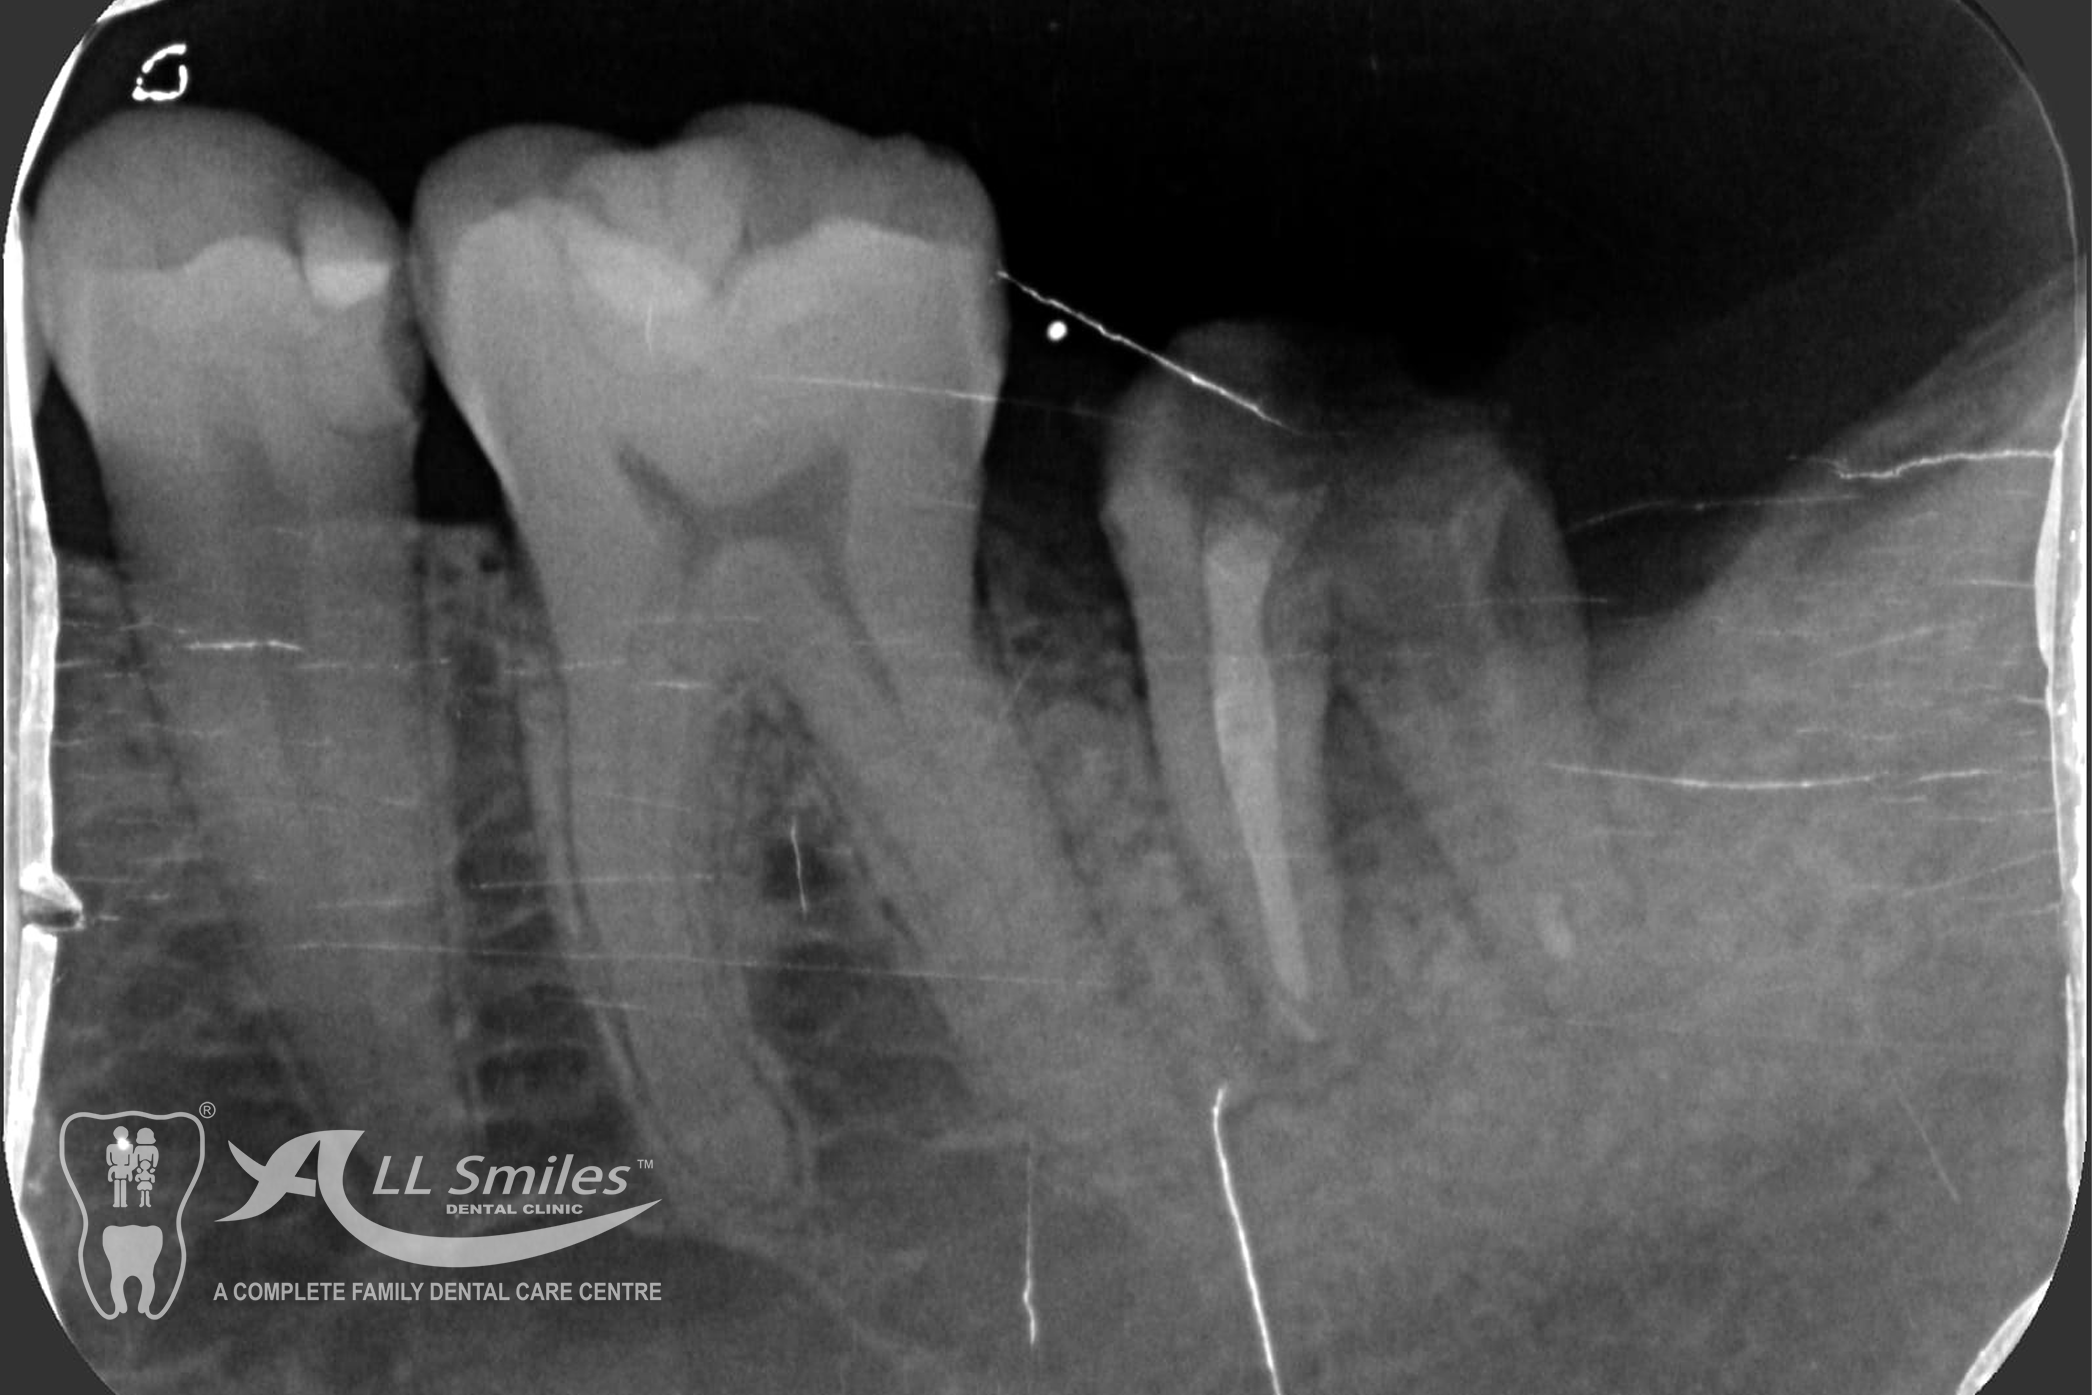

Successful tooth implant procedures require a foundation of healthy bone and gums. Before starting an implant procedure, we’ll assess your health and work with you to create a plan to resolve gum disease or other issues. Expect your first visit to take about 90 minutes and include an exam, x-rays, thorough cleaning, and plenty of time to speak with your dentist.

The dental implant procedure is divided into stages. The first stage involves the placement of the implant into the jawbone, which usually takes 1-2 hours. After this, there is a healing period of 6-8 weeks during which the implant fuses with the surrounding bone tissue. Once the implant has healed, a small connector called an abutment is attached to the implant, followed by the attachment of a dental crown, bridge, or denture.